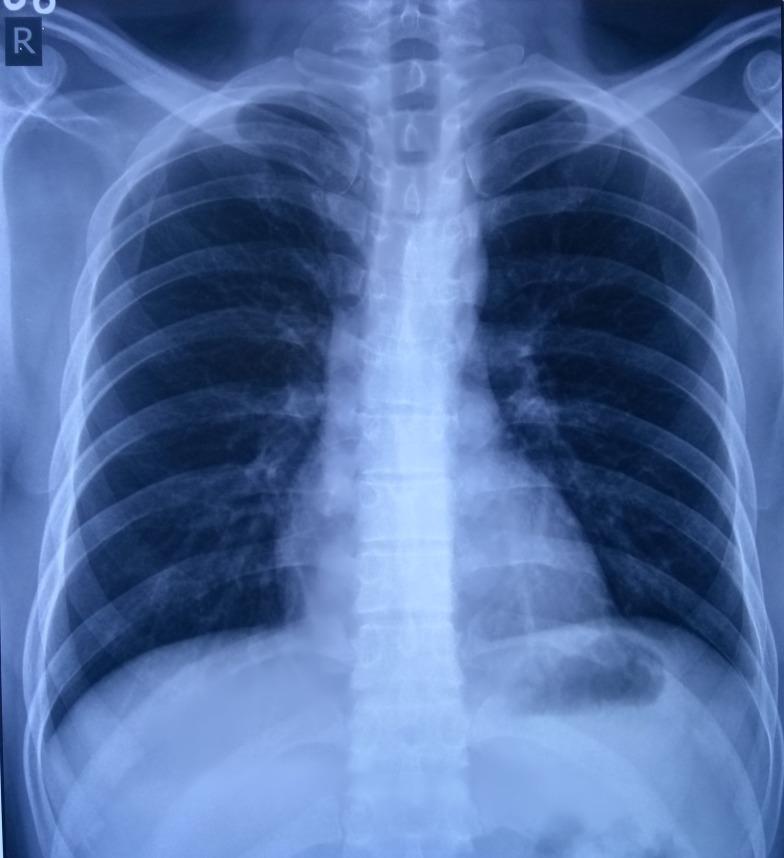

Belly dancer's dyskinesia (BDD) is an extremely rare manifestation consisting of involuntary and repetitive rhythmic movements of the abdominal wall. These movements cannot be voluntarily suppressed but may be influenced by respiratory maneuvers. Investigations such as spinal cord and abdominal imaging usually fail to reveal any local abnormalities to explain the movement disorder. A 23-year-old male presented with sudden onset of undulating movements of the abdominal wall for the last two months after he took domperidone. There was no associated pain or effect of respiration. The movements used to subside during sleep. His radiological and hematological evaluations were inconclusive. The movements, however, subsided after administration of promethazine and clonazepam. The cause of BDD varies, making diagnosis difficult. One of the causes being drug induced but it has never been reported earlier by domperidone. Also, our report provides a possible way to manage BDD by clonazepam and promethazine.

肚皮舞者运动障碍(BDD)是一种极为罕见的表现,其特征为腹壁出现不自主且重复的节律性运动。这些运动无法被自主抑制,但可能会受到呼吸动作的影响。诸如脊髓和腹部成像等检查通常无法发现任何局部异常来解释这种运动障碍。一名23岁男性在服用多潘立酮后,在过去两个月里突然出现腹壁起伏运动。没有伴随疼痛或呼吸影响。这些运动在睡眠时会平息。他的放射学和血液学评估结果不明确。然而,在给予异丙嗪和氯硝西泮后,这些运动平息了。BDD的病因各不相同,导致诊断困难。其中一个病因是药物诱发,但此前从未有过多潘立酮诱发的报道。此外,我们的报告提供了一种用氯硝西泮和异丙嗪治疗BDD的可能方法。